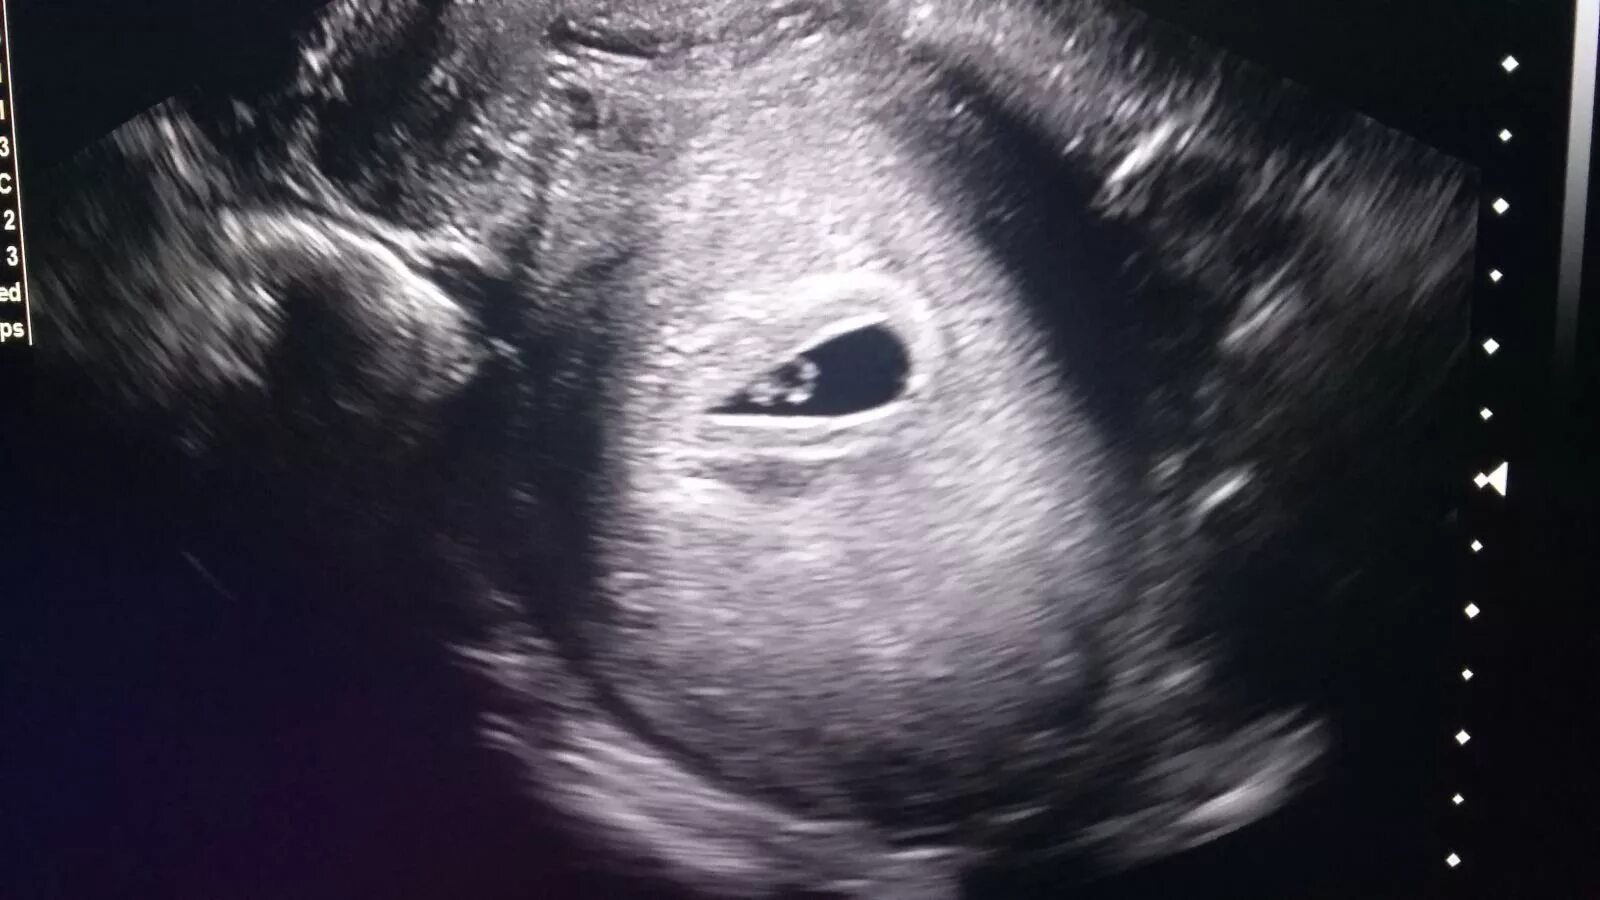

Узи 6 месяцев